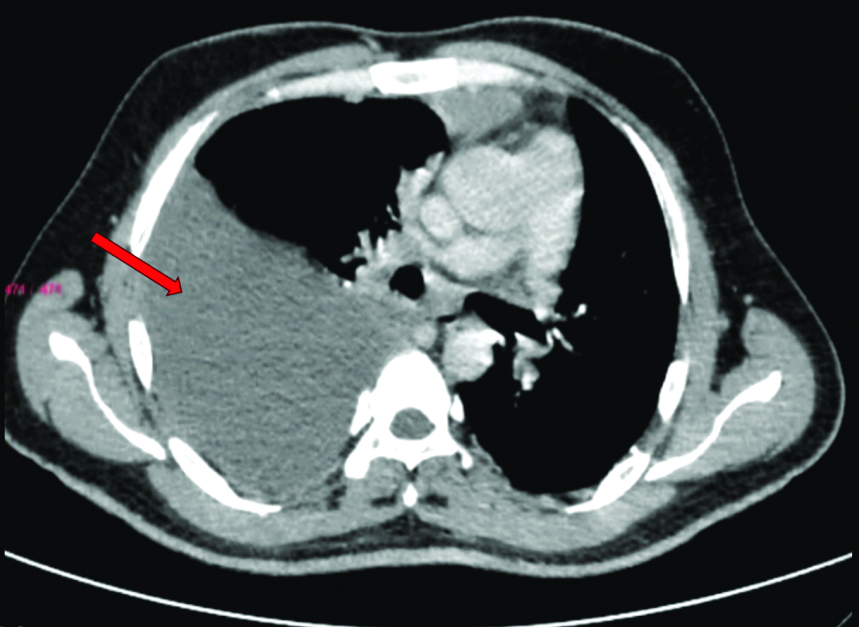

Radiological investigations included a chest X-ray showing right middle and lower zone homogeneous opacity obliterating the right cardiophrenic and costophrenic angles, suggestive of right pleural effusion [Table/Fig-2]. An ultrasound of the thorax indicated a gross right pleural effusion (>1000 cc) with internal septations. High-Resolution Computed Tomography (HRCT) and CT Pulmonary Angiogram (CTPA) confirmed the gross right pleural effusion without evidence of thromboembolism [Table/Fig-3]. It showed a large abnormal communication between the left distal ascending aorta and the right wall of the main pulmonary artery [Table/Fig-4].

CTPA thorax suggestive of Gross right-sided pleural effusion (red arrow).

CT pulmonary angiography showing a large abnormal communication between the left distal ascending aorta and the right wall of the mail pulmonary artery.